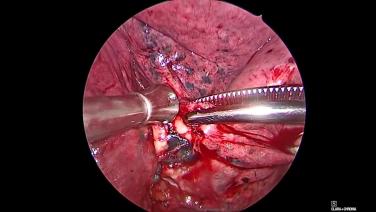

Thorascopic Lobectomy - Staple and Divide the Lobar Bronchus